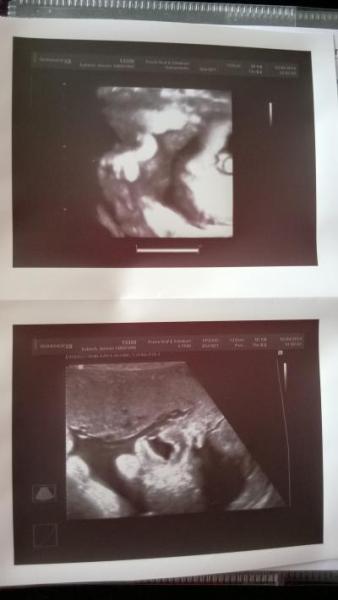

Hallo Mädels, Der neue FA ist der Hammer... schade das er Schwul ist, in den könnte man sich echt verlieben. Also aber mal von vorn.... Der FA hat bemerkt das der ET bereits in der 10. Woche vordatiert wurde und von den Maßen bisher, ist er der Meinung das wir den auch nehmen sollten. Da der kleine immer 1-2 Wochen größer war bisher. Somit bin ich heute genau 34+0. Willkommen Mutterschutz, Willkommen 35. Woche. Zum CTG: Die Herztöne waren Top. gab schöne 9 Punkte. Aber es waren kleine Kontraktionen zu sehen. Viele kleine. Mindestens 7 in den 20 min. Der FA sagt aber das es keine Wehen sind. Das würden bei mir richtig große Kurven sein da ich so schmal bin. Er hat mir sogar erklärt wie man im CTG auf die Punkte kommt. Wusste ich bisher gar nicht... Zum US: Papa war dabei. Das erste mal überhaupt hat er seinen Sohn live gesehen. Ein paar Tränchen sind gerollt. Ich hab sie gesehen, auch wenn er es abstreitet. Der kleine Mann ist weiterhin ein Junge. Er wiegt nun gute 2750 gramm. Es ist ein strammes Bürschchen. Maße waren KU: 31,7 FL: 6,3 entspricht 44,1 cm. Der FA schätzt das der kleine wenn er denn bis Termin wartet mindestens 50 cm groß sein wird, allerdings keine 55 cm erreicht. Und vom Gewicht her wird er 3300 - 3700 gramm, wenn er denn bis ET wartet. am 14.4 darf ich wieder hin. Da möchte er nach dem Muttermund schauen. Und gucken ob wir es über Ostern überhaupt schaffen. Sollte mir die Blase springen, darf ich in ruhe ins KH fahren. Der kleine liegt fest im Becken. Vom Gewicht her darf er kommen meinte der FA. Da er kein Untergewicht mehr hätte. Achja Bilder hab ich ran gehangen. Der kleine Mann war sehr genervt von unserem Termin, er hat andauernd gegähnt und die Schnute verzogen. Das war total süß. Da war selbst der FA total entzückt. Lieben Gruß von der ganz verliebten Doreen die total unerwartet nun die 35. Woche beginnen darf...

Bild zu Ich bin verliebt,..... Tollster FA Termin überhaupt... - Forum für Mai - Mamis

Hört sich ja alles Supi an...und die Bilder sind der Hammer!!!!!

Das ist super dass du für die letzten wochen und später noch einen fa gefunden hast bei dem du dich wohl fühlst. Die Bilder sind toll geworden. Lg